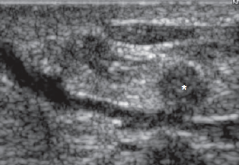

Fibroadenoma

Oval or macrolobulated mass

Hypoechoic

Well circumscribed/ smooth margins

Homogeneous

Wider than tall

Posterior enhancement

Can have:

• *- Calcifications**

• *- Internal vascularity**